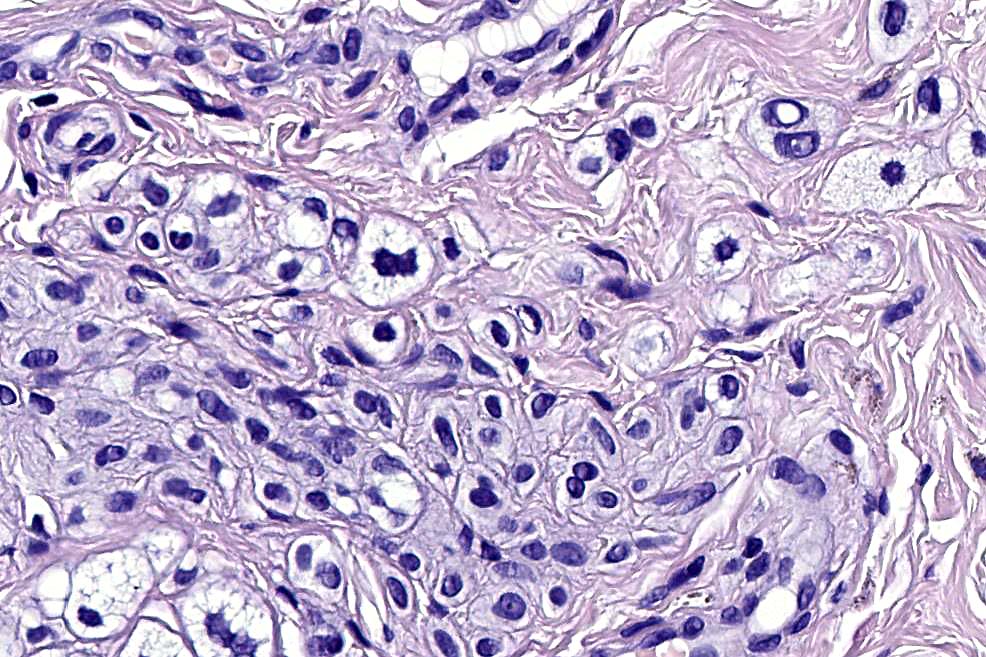

.Balloon cell nevs genrally has uniform, hyperchromatic nuceli (as opposed to the vesicular nuclei with prominent nucleoli) seen in melanoma. Mitoses are absent.(In my experience, balloon cell melanoma is more common than balloon cell nevus).

The importance of the entity is that it must always be distinguished from balloon cell melanoma. All cases should be scrutinized very carefully for pleomorphism and mitotic activiy before rendering a diagnosis of balloon cell nevus.